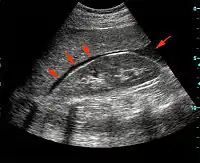

Focused assessment with sonography in trauma (commonly abbreviated as FAST) is a rapid bedside ultrasound examination performed by surgeons, emergency physicians, and certain paramedics as a screening test for blood around the heart (pericardial effusion) or abdominal organs (hemoperitoneum) after trauma.[1]

The four classic areas that are examined for free fluid are the perihepatic space (including Morison's pouch or the hepatorenal recess), perisplenic space, pericardium, and the pelvis. With this technique it is possible to identify the presence of intraperitoneal or pericardial free fluid. In the context of traumatic injury, this fluid will usually be due to bleeding.

FAST is most useful in trauma patients who are hemodynamically unstable. A positive FAST result is defined as the appearance of a dark ("anechoic") strip in the dependent areas of the peritoneum. In the right upper quadrant this typically appears in Morison's Pouch (between the liver and kidney). This location is most useful as it is the place where fluid will collect with a supine patient. In the left upper quadrant, blood may collect anywhere around the spleen (perisplenic space). In the pelvis, blood generally pools behind the bladder (in the rectovesicular space). A positive result suggests hemoperitoneum; often CT scan will be performed if the patient is stable[18] or a laparotomy if unstable. In those with a negative FAST result, a search for extra-abdominal sources of bleeding may still need to be performed.